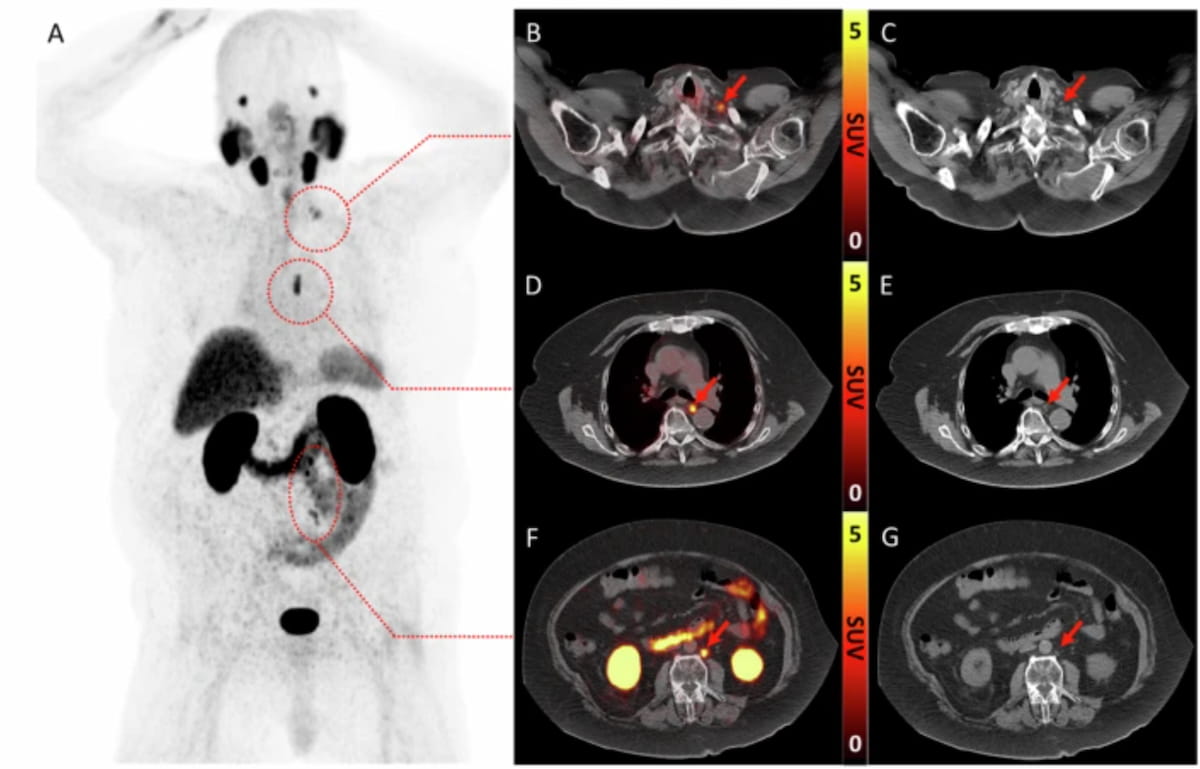

PSMA PET offered 18 percent higher accuracy for detecting biochemical recurrence of PCa in contrast to mpMRI, according to findings from a 67-study meta-analysis.